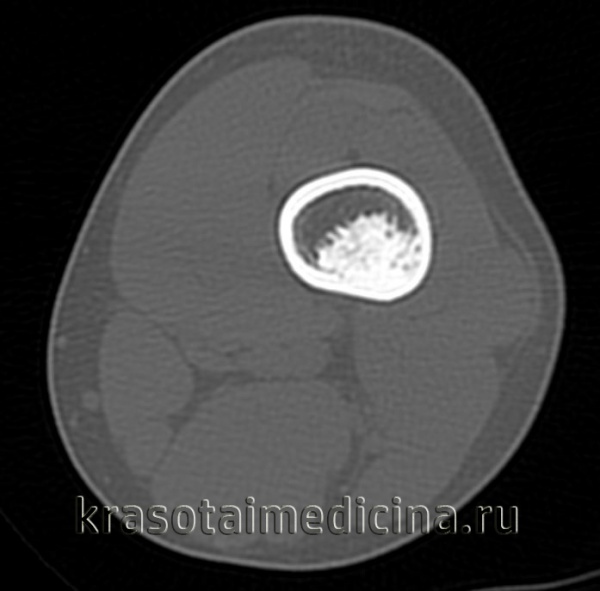

- Рентгенография кости. На снимках визуализируется кистообразные изменения или неоплазия в виде «мыльных пузырей» в метафизарной зоне. Признаки общего остеопороза отсутствуют, вокруг измененного участка может просматриваться остеосклероз. Границы доброкачественной ГКО более четкие, но из-за местно-агрессивного роста при значительном размере возможно появление «костного козырька». Выраженная периостальная реакция нехарактерна. Злокачественная остеокластома имеет нечеткую структуру. На снимках рано обнаруживается разрушение кортикального слоя.

- КТ и МРТ кости. Компьютерная томография дает более четкое представление о форме, размерах, границах гигантоклеточной опухоли, в сомнительных случаях позволяет подтвердить или опровергнуть разрыв коркового слоя. В ходе магнитно-резонансной томографии исследуют интрамедуллярный и кистозный компоненты, оценивают состояние окружающих мягких тканей, расположение сосудов и нервов. Методики помогают выбрать оптимальный вариант хирургического вмешательства, спланировать операцию.

КТ левого бедра. Объемное образование (оссифицированная энхондрома) в нижней трети диафиза бедренной кости.